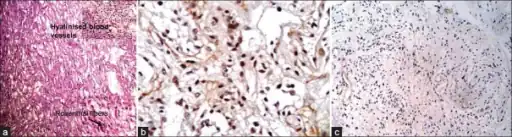

- a-c) Photomicrograph shows microcystic areas in pilocytic astrocytoma

Under the microscope, the tumor is seen to be composed of bipolar cells with long "hair-like" GFAP-positive processes, giving the designation "pilocytic" (that is, made up of cells that look like fibers when viewed under a microscope[6]). Some pilocytic astrocytomas may be more fibrillary and dense in composition. The presence of Rosenthal fibers,[7] eosinophilic granular bodies, and microcysts can often be seen. Myxoid foci and oligodendroglioma-like cells may also be present, though these are not specific to pilocytic astrocytoma. Long-standing lesions may show hemosiderin-laden macrophages and calcifications.